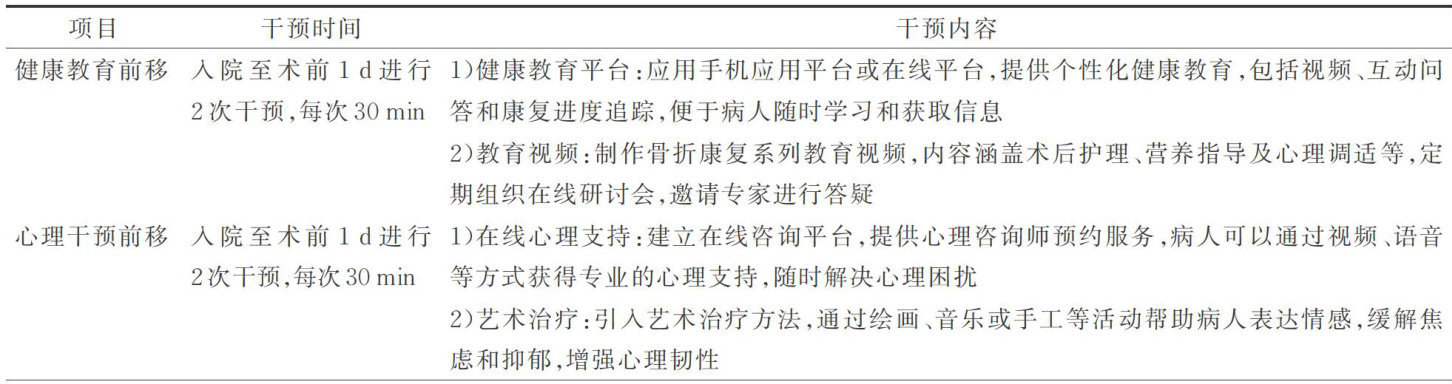

综合研究 | 基于康复前移理念的护理干预在老年股骨转子间骨折病人中的应用

综合研究 | 基于康复前移理念的护理干预在老年股骨转子间骨折病人中的应用